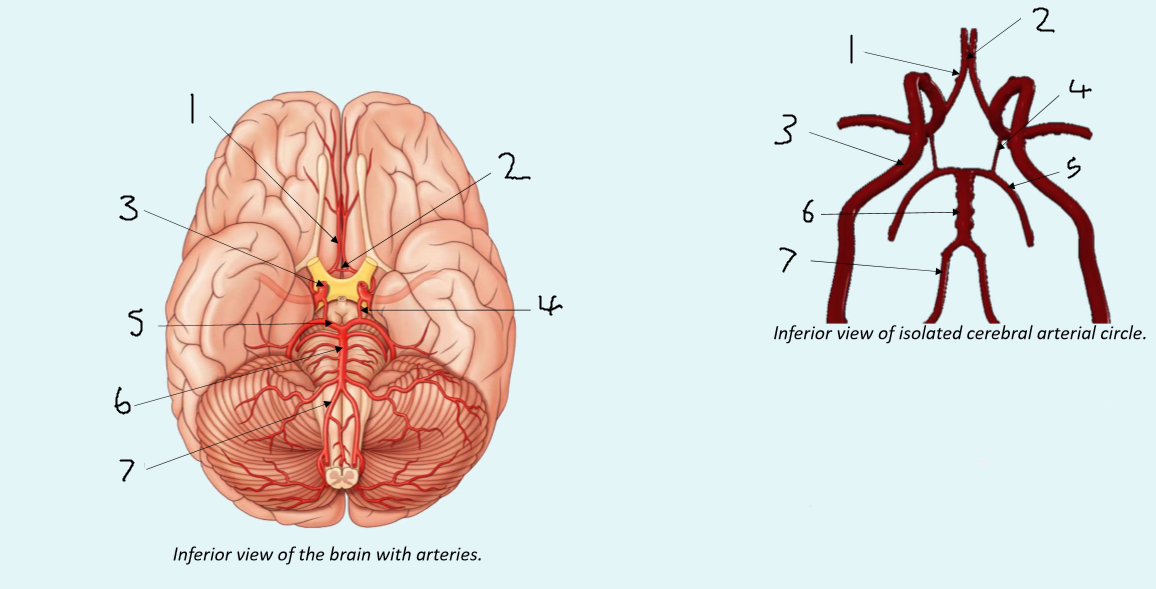

What is 1?

anterior cerebral artery

What is 2?

anterior communicating artery

What is 3?

internal carotid artery

What is 4?

posterior communicating artery

What is 5?

posterior cerebral artery

What is 6?

basilar artery

What is 7?

vertebral artery

What is 1?

anterior communicating artery

What is 2?

anterior cerebral artery

What is 3?

middle cerebral artery

What is 4?

internal carotid artery

What is 5?

posterior communicating artery

What is 6?

posterior cerebral artery

What is 7?

superior cerebellar artery